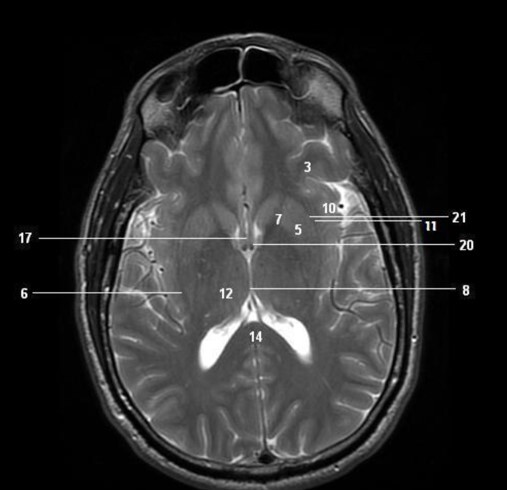

Label 1-6

Label 2,3,4,5,7,8

2=Rt Caudate nucleus

3=Corpus callosum

4=Lt lateral ventricle

5=Third ventricle

7= Septum Pellucidum

8= Rt Interventricular foramen

Label 3,5,7,10,11,12,14,20

3=Lt frontal lobe

5=Lt Lentiform nucleus

7=Lt internal capsule

10=Insula

11=Lt Claustrum

12=Rt Thalamus

14=Splenium, CC

20=Lt Interventricular foramen